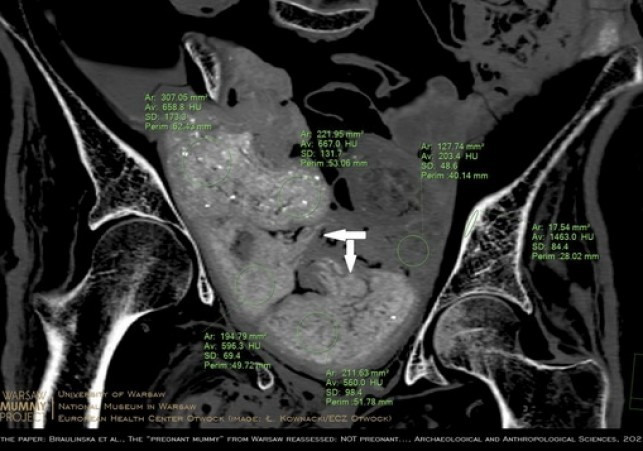

W lipcu 2022 ukazała się bogato ilustrowana publikacja w "Archeological and Anthropological Sciences" (DOI: 10.1007/s12520-022-01598-z), w której inny zespół badaczy z WMP dowodzi, że zmumifikowana kobieta z pewnością nie zawiera w sobie płodu. Świadczą o tym przede wszystkim obrazy precyzyjnie zrekonstruowanej zawartości miednicy oraz wyniki badań porównawczych starożytnych płodów egipskich.

Naukowcy ustalili, że w miednicy wcale nie ma płodu - jak sugerowali autorzy doniesienia z 2021 r. - ale cztery pakunki.

To właśnie trzy z czterech pakunków w miednicy poprzedni zespół zinterpretował jako płód. O tym, że kobieta nie była w ciąży, świadczą też ilościowe pomiary gęstości radiologicznych, a także wzajemne relacje geometryczne pakunków oraz porównawcza charakterystyka materiałów znajdujących się wewnątrz mumii - argumentują badacze w nowo opublikowanym artykule.